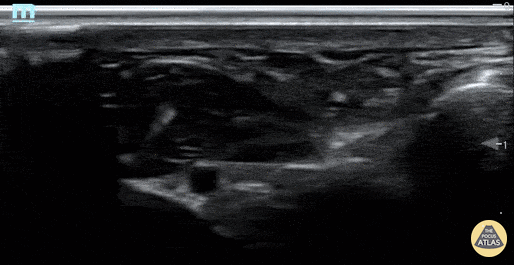

Ulnar nerve block done in plane. Provides excellent anesthetic for isolated hand injuries. In this case, allowed for faster time to repair and avoided use of ketamine sedation. Inject in place and use small amounts of lidocaine to make sure you are in the correct space before bathing the nerve with the entire amount of anesthetic. Julia Brant, Pediatric Emergency Medicine Fellow @pedipocus